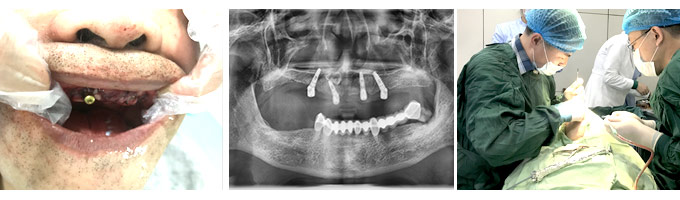

经过详细的口腔检查后,我发现刘大爷的牙槽骨萎缩严重,还患有骨质疏松。牙周病会让牙槽骨萎缩、骨质流失、牙松脱落。牙周病也会影响种植牙成活率,应先治牙周病,再种牙。

做完牙周治疗,我们为刘大爷制定了即刻种植方案,这个方案是专为50岁以上的中老年人设计的,大的优势是对骨量的要求不高,不需植骨也能种牙,尤其适合牙槽骨条件不好,有骨质疏松的人群,且全程微创无痛,治疗时间短。术后,刘大爷表示后悔没早点来种牙,现在晚年幸福终于有了很大的保障,想吃什么就吃什么。

即刻种植牙,是康贝佳口腔的特色种牙方式。它的特点是对骨量的要求不高,不需植骨也能种牙。而且当天种牙当天就有牙用。因为采用了体积更小的植体,医生在植入牙槽骨时更为精准;骨愈合面减小,骨结合也自然更快,这让种植牙手术变得简单、轻松!